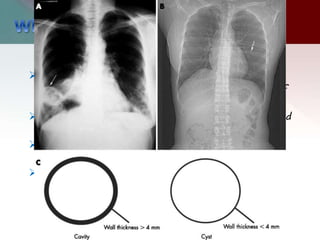

 A cyst is a round space defined pathologically

by an epithelial or fibrous outer wall and

radiologically as a round parenchymal lucency

or low attenuation area with a well defined

interface with normal tissue.

 surrounded by a thin (2mm or less ) wall.

 A bleb or bulla has a wall that is less than 1

mm.

 Pulmonary cavities are gas-filled areas of the

lung in the center of a nodule, mass, or area of

consolidation.

 They are usually evident on plain radiography and

CT.

 They are typically thick walled and their walls

must be greater than 2-5 mm.